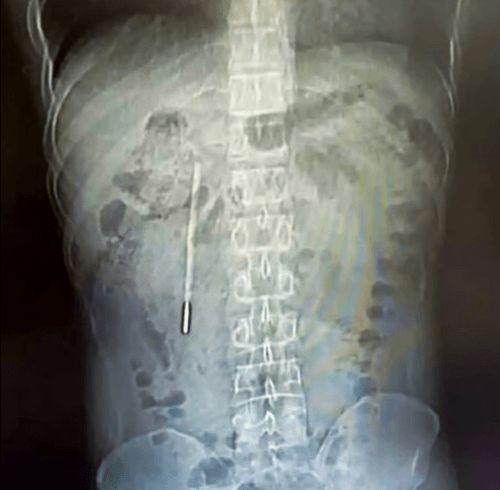

Uşaq vaxtı udduğu termometr  – 20 il sonra çıxarıldı

Vanqın mədəsində yad bir cisim görülüb ki, bu da civə termometri kimi müəyyən edilib. Çaşqınlıq içində olan Vanq 12 yaşında soyuqdəymə keçirəndə ağzında tutduğu termometri təsadüfən udduğunu deyir. Qorxmuş oğlan valideynlərinə bunu deməyib, valideynləri isə termometri unutmuşlar. Yalnız 20 il sonra eyni termometr 32 yaşlı kişini narahat etməyə başlayıb.

Cərrahlar yad cismi cəmi 20 dəqiqə ərzində çıxardılar. Əməliyyat olduqca həssas idi, çünki termometr uzun müddət xəstənin bədənində idi və öd yollarına yaxın yerləşirdi. Xoşbəxtlikdən termometr bütöv çıxarıldı.